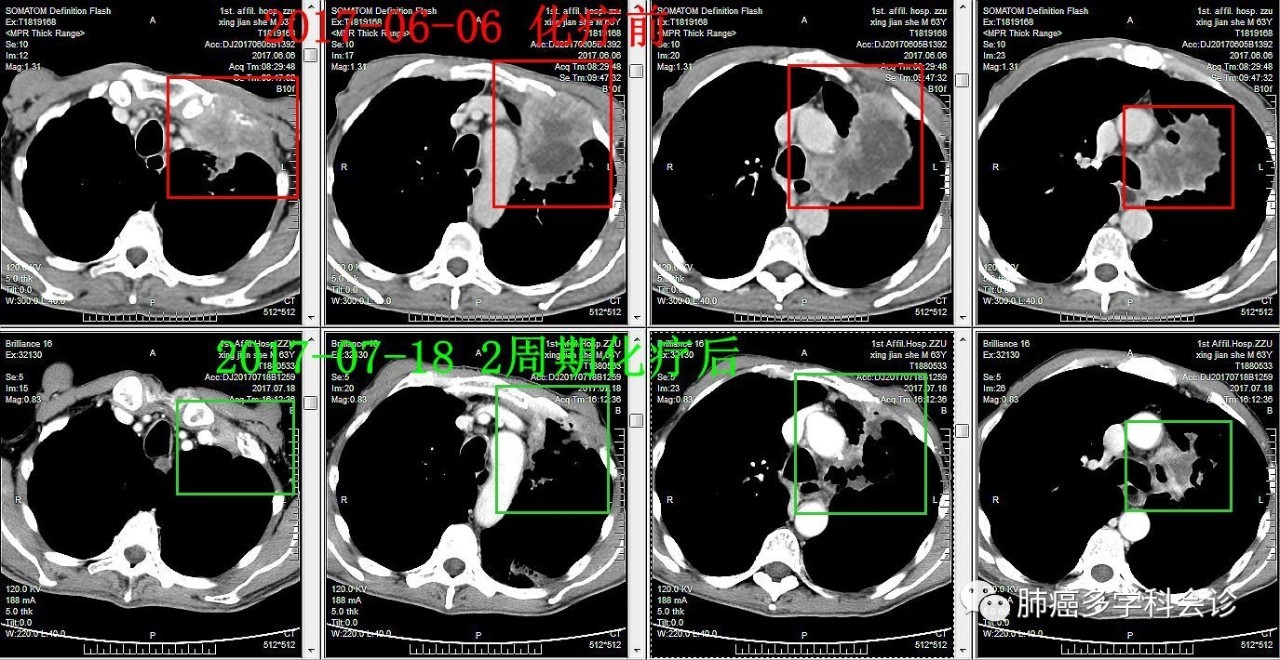

患者邢JS,男,63岁,咳嗽伴左胸隐痛1月余。

• CT 示:左上肺门肿瘤侵犯胸壁,第一胸肋关节受累,左肺上叶不张、实变。

临床诊断:左肺鳞癌 ⅢB 期

于2017-6-8、2017-6-29接受“紫杉醇胶束+顺铂”化疗第 1、2 周期,过程顺利。2周期化疗后肿瘤明显退缩,获部分缓解。继续完成计划的 6 周期化疗。

以下是该患者化疗前后相隔 42 天的胸部 CT 对比,肿瘤明显退缩: